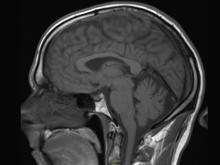

New research, published in the journal Radiology, suggests some types of a popular contrast agent used in magnetic resonance imaging (MRI) exams may remain in the brain for years, but that the long-term effects are unknown.